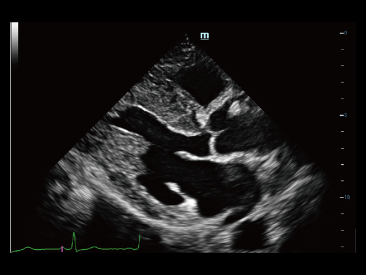

Desde que se fund├│ la compa?├Ła, Mindray ha explorado incansablemente nuevas formas de mejorar la confiabilidad del diagn├│stico. Con la revolucionaria tecnolog├Ła de ZONE Sonography?, la nueva plataforma ZST+ de Resona?7 lleva la calidad de la imagen por ecograf├Ła a un nivel superior mediante el procesamiento de datos de canal y la adquisici├│n de zona.

Adem├Īs de la calidad de imagen de primer nivel, Resona?7 tambi├®n mejora las capacidades de investigaci├│n cl├Łnica con el revolucionario V?Flow para la evaluaci├│n hemodin├Īmica vascular y con la adquisici├│n de planos m├Īs inteligente a partir de conjuntos de datos 3D para el diagn├│stico del SNC fetal. Al combinar el funcionamiento multit├Īctil basado en gestos m├Īs intuitivo y todas las caracter├Łsticas cl├Łnicas esenciales, Resona?7 realmente lidera las novedades en innovaci├│n de ecograf├Łas.